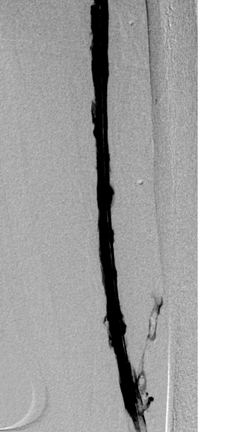

Vena femoral izquierda duplicada, vena femoral común izquierda y VCI de la vena ilíaca externa tras trombectomía mediante el catéter Solent de AngioJet; 25 mg tPa en 250 cc de solución salina (Rapid Lysis) y stent de 14 mm.

Stent de 14 mm implantado.